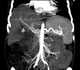

Pseudoaneurysm of hepatic artery

A pseudoaneurysm, also known as a false aneurysm, is a collection of blood that forms between the two outer layers of an artery, the tunica media and the tunica adventitia. It is usually caused by a penetrating injury to the vessel, which then bleeds, but forms a space between the above two layers, rather than exiting the vessel. [Source: Wikipedia ]